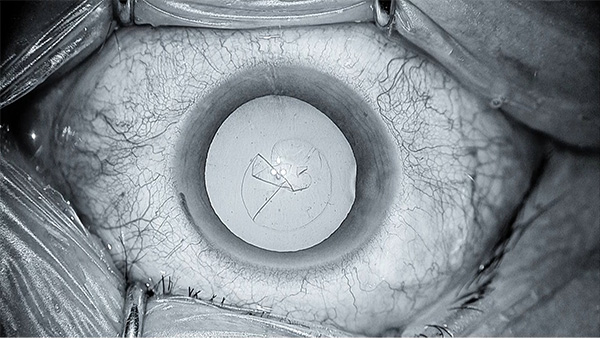

前眼部の白内障手術では、モノクローム表示して水晶体を包んでいる膜の色/カラーは薄く青みがかった状態になり、構造/ストラクチャーが強調されます。CAS機能がOFFの状態では平面的に見えていたものが、ONにすると奥まで透けて立体的に見え、層に重なった透明な膜も前後の位置関係がはっきりと区別できます。混濁に隠れてわかりにくいエッジの部分も、ストラクチャーを+1強調するだけでとてもわかりやすく、切開しやすくなります。

CAS機能ON(青みがかった状態)

CAS機能OFF(平面的に見える)